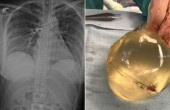

Канад улсын Торонтод 2018 онд гарсан хэргийг мэргэжилтнүүд анагаах ухааны талаас дахин судалжээ. Тус хотод бууны суманд оногдсон 30 настай эмэгтэй цээжиндээ буудуулсан ч амь нас нь аврагдсан байна. Эмэгтэйн хиймэл хөх сумны чигийг өөрчилснөөр түүний амь насыг аварсан гэж судлаачид Sage анагаах ухааны сэтгүүлд хэвлүүлсэн нийтлэлдээ онцолжээ.